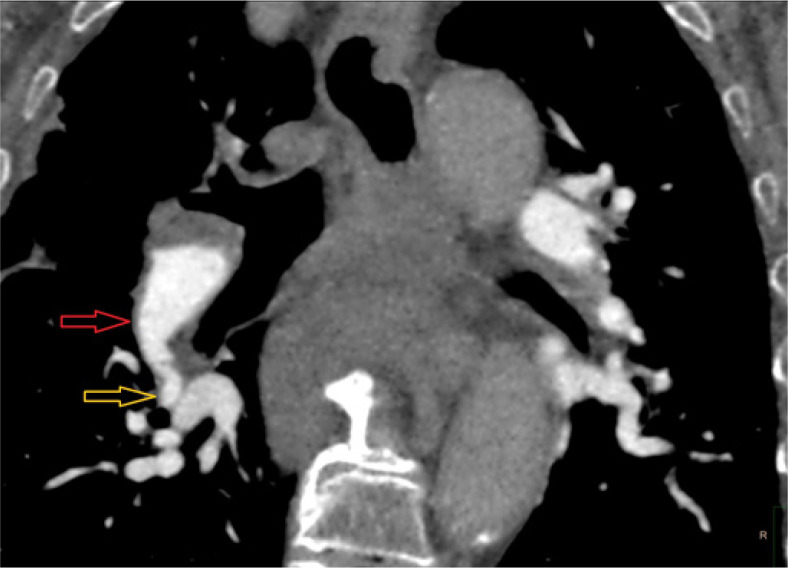

Results: CTEPH patients exhibited vessel narrowing, intimal irregularities, bands, and webs in all cases (100%), with the highest diagnostic value at the segmental level (AUC = 0.906). Mosaic perfusion and variability in vessel size demonstrated moderate predictive value (AUC = 0.740 and AUC = 0.788, respectively).